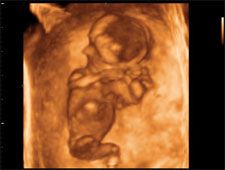

2D/3D/4D ultrahang

Rendelőnkben a legmodernebb technikával, a Medison SonoAceX8-as készülékkel végezzük a vizsgálatokat. Ez a korszerű, nagy felbontású gép 2D, 3D és 4D ultrahangos képességgel is rendelkezik, így lehetőség van az összes, szülészet-nőgyógyászatban fontos ultrahangos vizsgálat elvégzésére:

Vizsgálatainkat előbb 2D technikával végezzük el. Ez a „hagyományos" ultrahang kép 2 dimenzióban, azaz a síkban ábrázolja a vizsgált területet. Ez a mód a legalkalmasabb a magzat egészségi állapotának felmérésére, az esetleges eltérések észlelésére.

A 3D technikánál az ultrahang gépben levő számítógép, a vizsgálófej által gyors egymásutánban letapogatott síkokból képez egy virtuális 3 dimenziós képet. Ezt a valósághű képet árnyékolással, a szín erősségének változásával éri el.

Az ultrahang gépek fejlődésével megjelent a 4. dimenzió is, ami nem más, mint az idő. 4D technikánál a 3D-hez hasonló virtuális eredményt kapunk, de itt mindezt mozgóképként láthatjuk a készülék monitorján.

A 3D és 4D technika sokat segít a magzat külalakjának vizsgálatakor, jól látható a fej az arc, a test, így a magzat neme is könnyebben állapítható meg. Az így készült képek, mozgóképek nagy élményt jelenthetnek a szülőknek, babájuk csaknem megfoghatóvá válik a vizsgálat során. Ugyanakkor a képek minősége nagyban függ a magzat elhelyezkedésétől, illetve mozgásától is.